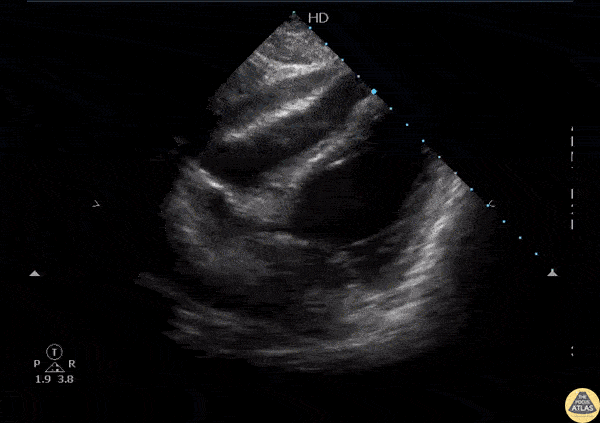

Pericardial Disease - Hemopericardium

A young previously healthy male presented to the ED with a transmediastinal gunshot wound. FAST exam revealed hemopericardium on the subxiphoid window. Image courtesy of Robert Jones DO, FACEP @RJonesSonoEM Director, Emergency Ultrasound; MetroHealth Medical Center; Professor, Case Western Reserve Medical School, Cleveland, OH View his original post here